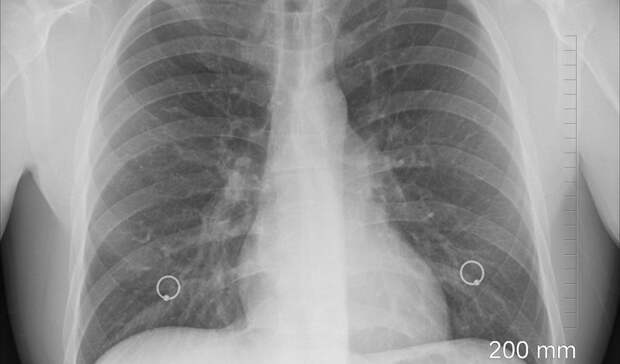

Как рассказал спикер, у 86 из 173 пациентов диагностировали пневмонию: таким образом, у половины заразившихся коронавирус вызвал осложнения с легкими. Также известно, что у 68 человек болезнь проходит бессимптомно, а у 19 пациентов наблюдаются характерные для ОРВИ симптомы.